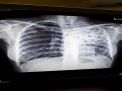

Kajian Dampak Pandemi COVID 19 terhadap Pengendalian Tuberkulosis